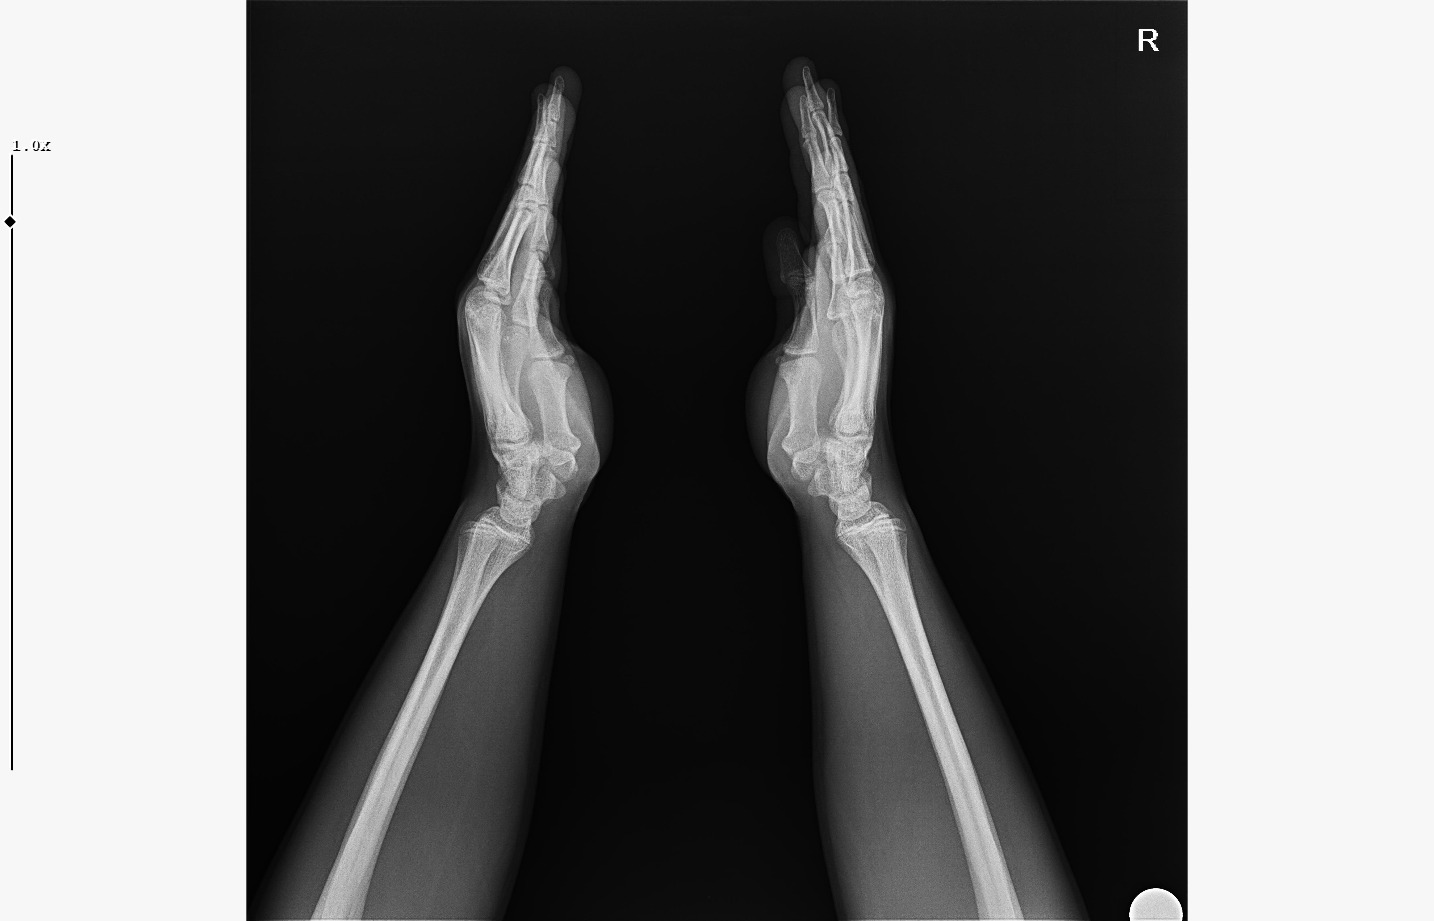

doktor bi sik bilmiyodur büyük ihtimalle plakları buraya at biz bakak

röntgeni atar mısın?

• WhatsApp Image 2026-01-07 at 00.31.08 (4).jpeg

WhatsApp Image 2026-01-07 at 00.31.08 (4).jpeg

161.8 KB · Views: 0

• WhatsApp Image 2026-01-07 at 00.31.08 (3).jpeg

WhatsApp Image 2026-01-07 at 00.31.08 (3).jpeg

104.8 KB · Views: 0

bilmiyo zaten,ki el plakları boy ile neredeyse hicbirsey göstermiyo bile ama tr de hangi doktora gidersen git %95inden fazlası el plağına bakcak ona göre yorum yapcak

kapanmaya baslamıs ama cok yakın degil

kemik yaşın 15 gibi 15'e çok yakın

anne baba boyun ve yaşını bilmiyorum sadece bu bilgilerle 171-175 arası diye tahmin ediyorum röntgen ile.

normalde anne babana göre 171-176 olman gerek zaten. kemik yaşın ve şuanki boyun ile yapılacak tahmin anne baban ile yapılabilecek tahminle nerdeyse birebir aynı yani büyük ihtimal o civarlar olursun bence